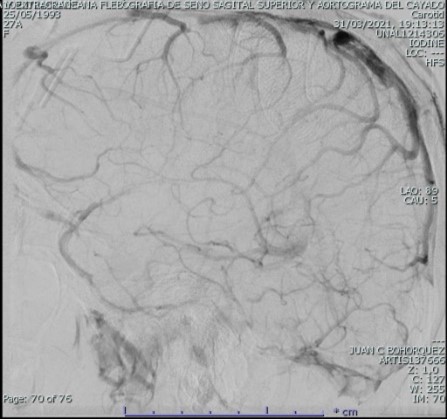

El examen físico inicial sin alteración neurológica; sin embargo dado cuadro clínico se enfoca como cefalea con banderas rojas con sospecha de hipertensión intracraneal, se toma tomografía de cráneo simple con hallazgo de trombosis del seno sagital superior con extensión hacia el seno transverso derecho y hacia la región proximal del seno sigmoideo ipsilateral, con discreto edema difuso de los lóbulos occipital, parietal y región posterior del lóbulo temporal ipsilateral; se inicia anticoagulación con heparina de bajo peso molecular a 1 mg/kg cada 12 horas y se decide caracterización con panagiografía cerebral temprana y evaluar beneficio de neurointervención, la cual muestra extensa trombosis de senos durales, longitudinal superior en sus dos tercios posteriores, tórcula, seno transverso y seno sigmoideo derecho con extensión a yugular derecha, con signos de hipertensión venosa. Se realiza tromboaspiración de senos durales con recanalización completa de seno transverso y sigmoideo derecho, así como de tórcula y vena yugular tercio proximal derecho, recanalización parcial de seno longitudinal superior con persistencia de trombos murales adherentes con marcada mejoría en el flujo anterógrado, continuo en vigilancia en cuidados intensivos.